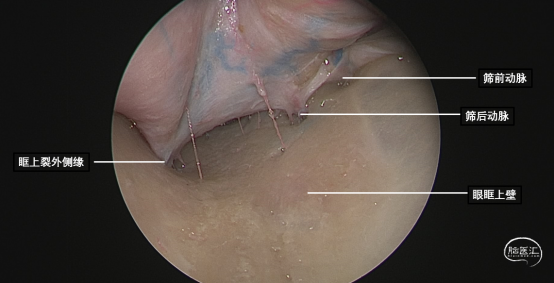

研究表明此入路除细小的滋养血管外无其他重要结构!皮肤切口选择近眶缘眉弓美容切口,紧贴眶上壁分离骨膜,保护眶筋膜,病变紧贴眶上壁,导航下确定眶尖紧贴眶上壁的病变,外观呈浅紫兰色,考虑既往有出血所致,显露肿瘤!

球后眶尖部位及海绵窦区的病变因为位置深在,周围重要结构众多,对神经外科医生具有极高的挑战性。神经内镜技术发展给我们提供了一条思路。我们通过相关解剖研究发现,病变位于海绵窦外侧壁、颈内动脉外侧、颞极内侧,可选择经眶外侧壁入路;病变位于眶尖内侧,累及海绵窦侧壁,经眶内侧壁入路更为适合;病变主体位于鞍区向一侧海绵窦侧壁侵袭,可以考虑内镜经鼻入路。眶内上壁病变,因为无重要结构,经眶入路最适合!